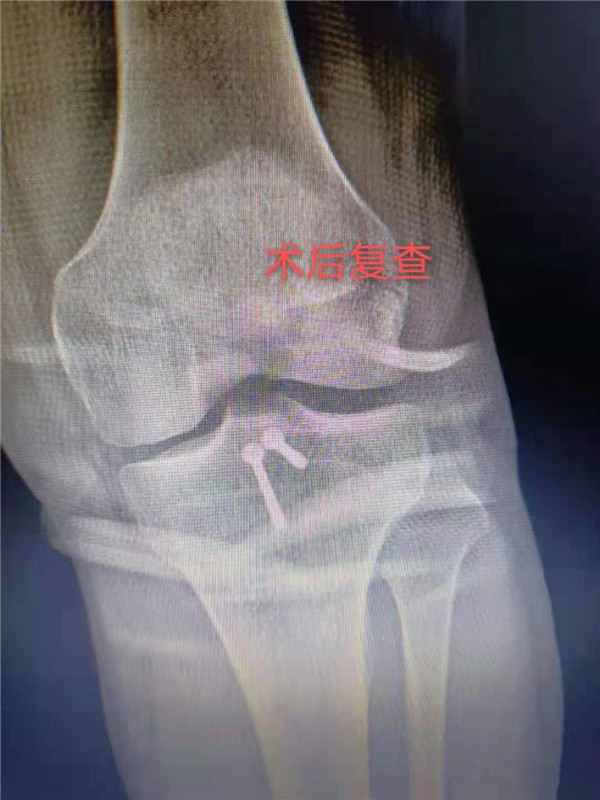

患者李某,今年37岁,因几日前跨越障碍物时不慎摔倒,左膝着地,当即觉得左膝疼痛难忍、活动受限。于12月1日入市三院就诊,入院后查左膝正侧位片、左膝CT三维重建等检查:提示后交叉韧带止点撕脱性骨折。经骨一科主任邵建敏和副主任医师徐军志反复查阅相关资料及科室病例讨论后,充分与患者及家属沟通并征得同意后,建议行改良小切口下行止点重建术。徐军志副主任医师于12月2 日在腰硬联合麻醉下为患者行左膝后叉止点撕脱性骨折复位内固定止点重建术,术后切口长约3CM。术后患者无不适感,症状明显改善,疼痛明显缓解,并于术后2天出院。